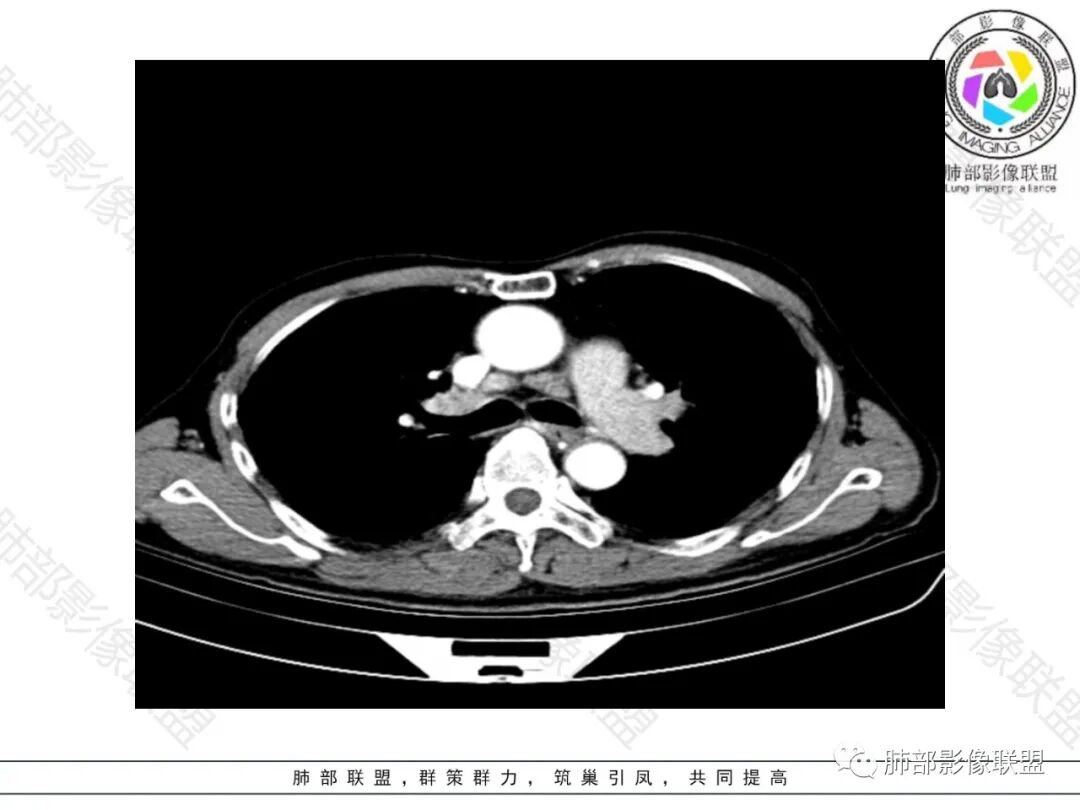

双肺慢支肺气肿。右肺下叶大片状影,支气管狭窄,枯枝状。间杂网格状影,实变影(与胸膜糊墙),叶间裂膨隆。右肺门增大。增强后右下肺片状影内血管束失去正常形态,边缘模糊。实变影不均匀强化。纵隔及右肺门多组淋巴结肿大,其中右侧10、11、12组淋巴结肿大内见液化。考虑肺炎型肺癌并感染?不典型结核待除外。左下小片影?(层面不全)。

右肺下叶大团块影,斜裂膨隆,内支气管破坏,纵隔窗实质性成份少有强化(假大空),肿瘤CA125、199高,考虑粘液腺Ca右肺门淋巴结及纵隔淋巴结大,右肺下动干起始处充盈缺损(示栓塞或Ca栓;余肺叶弥散网格状改变,间质增厚及纤维化表现!

老年男性,反复咳嗽咳痰喘憋8年,加重10天,发热半天。白细胞计数明显升高(存在细菌感染可能),CEA、CA19—9升高(肺癌或间质性肺疾病引起可能)。痰培养见肺克。CT;双肺弥漫小叶间质、中轴间质增厚,胸膜下肺气肿,右肺门及右下叶可见实变影,边界模糊,内支气管走形僵硬,部分见蜂窝样改变,增强后实变区可见低密度区(粘液?),叶间裂膨隆,纵隔及右肺门见肿大淋巴结,右肺门淋巴结内见坏死。存在感染,但单纯感染难以解释支气管走行僵硬、实变内的低密度病灶,考虑恶性伴感染,肺炎性肺癌或黏液腺癌。

既往慢阻肺病史,反复加重,治疗有效,胸部影像提示双肺间隔旁型肺气肿,也符合基础性疾病。本次病程为喘息加重10天,发热半天,为急性病程,有白色痰,相关感染指标升高,但白细胞和CRP升高比例不同步,胸部影像右肺下叶大片实变影,有膨隆感,原有的空洞考虑既往的肺气肿区域未完全填充的原因。但右肺10-12组淋巴结肿大,其内有低密度影,成环形强化,中叶支气管,下叶支气管狭窄管壁浸润感,不能用普通感染解释,需要考虑局部鳞癌?结核?

右侧肺门淋巴结肿大,中央低密度;纵隔见轻度增大淋巴结。

3.综合分析:临床方面:慢性病程、急性发作,呼吸道症状伴发热,炎性指标升高,提示存在感染可能;CA199升高,但相对特异性不高。影像双肺气肿,右肺下叶蜂窝状改变明显,夹杂实变密度区,支气管相关但未见阻塞,较常见于感染性病变,如G-杆菌感染等。蜂窝影什么时候出现我们不得而知,实变区周边特征掩盖不清。

主要相关支气管未见明显截断,病灶内血管影较为完好,也较少见于肺鳞癌。